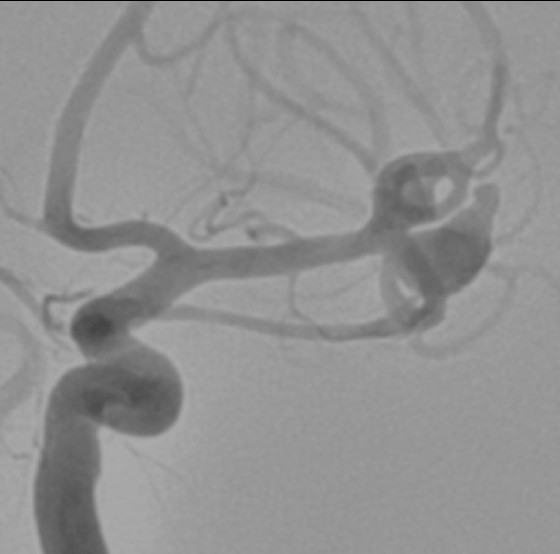

El gold standard para la identificación de la fuente del sangrado es la angiografía por sustracción digital convencional (ASD) porque tiene la mejor resolución para la detección de aneurismas y puede facilitar el tratamiento endovascular como parte del mismo procedimiento. Sin embargo, muchos centros utilizan imágenes no invasivas, como la angiografía por tomografía computarizada (AngioTC) o angiografía por resonancia magnética (ARM) como estudio inicial, reservando la ASD para los casos en que las imágenes no invasivas, no identifican la causa de la HSA.

Una ventaja importante de la ATC sobre la ASD es la rapidez y la facilidad con la que se puede obtener, a menudo inmediatamente después de que se realiza el diagnóstico de HSA mediante AngioTC cerebral el paciente todavía está en la sala de tomografía. La AngioTC se utiliza cada vez más como una alternativa a la DSA en muchos pacientes con HSA, evitando así la necesidad de ASD en algunos casos previo a la intervención [40,41]. Sin embargo, la ASD tiene la resolución más alta para detectar aneurismas intracraneales y definir sus características anatómicas, y sigue siendo el gold standard para el diagnóstico de aneurismas intracraneales [27,42]. Dado que un número cada vez mayor de aneurismas se tratan endovascularmente, otra ventaja de la ASD es la capacidad de diagnosticar y luego tratar definitivamente el aneurisma en la misma sesión.

La determinación exacta de la localización de un aneurisma cerebral roto es importante para la planificación del tratamiento, siendo la ASD el Gold standard para la detección del aneurisma [48]. La TC de cerebro inicial es el gold standard para detectar la HSA y evaluar su cantidad y distribución. Esta información es potencialmente útil para centrar la atención en alguna parte en particular de la circulación cerebral durante el estudio de ASD, disminuyendo así tiempo de estudio angiográfico y disminuyendo tiempo en la planificación del tratamiento. Cuando la ASD muestra múltiples aneurismas, la evaluación del patrón de sangrado puede ayudar a identificar cuál aneurisma sangró, ya que se han reportado casos de re-sangrados en pacientes con HSA aneurismática tratados por vía endovascular por mala interpretación del aneurisma que ocasionó el sangrado [49].